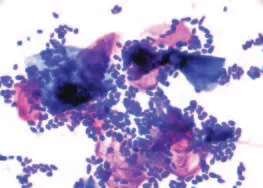

Bacteria: The most common bacteria found in ears are cocci (Staphylococcus, Streptococcus) and rods (Pseudomonas, Proteus). These bacteria are approximately 0.5 to 1.5 mcm in diameter (Figure 2).

Cocci and rods too numerous to count (modified Wright’s stain; original magnification, 100´; immersion oil)